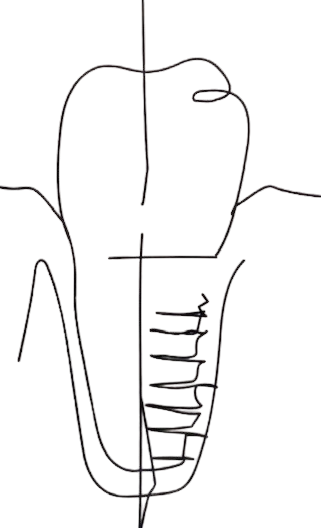

Allongement coronaire

Implant et régénération osseuse

Pose d'un implant simple